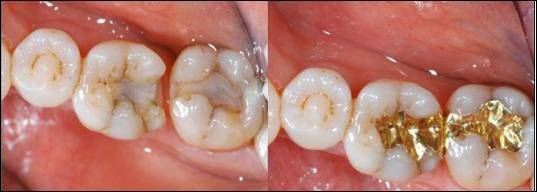

골드 인레이는 정확한 치면과의 접촉과 접착제를 이용한 부착으로 미세 누출이 적기 때문에 장기 예후면에서 가장 유리하다.

금이 장기간 치아 수복물로 애용되는 가장 큰 이유는 귀금속이라 부식이 적고 치아의 법랑질과 강도가 매우 흡사해 닳는 속도가 비슷하기 때문이다. 거기에 구강 밖에서 만들어지기 때문에 치아끼리 맞닿는 부분의 형태를 정확히 재현해 낼 수 있기에 음식물이 끼는 현상 역시 가장 적다.

골드 인레이의 단점은 우선 엄청난 고가에 있다. 다음으로 모든 재료 중 가장 많은 치아 삭제량과 비심미적이라는 단점 역시 가지고 있다.

환자가 경제적인 여유가 된다면 일반적으로 구치부 수복에서 가장 좋은 재료는 골드 인레이이다.